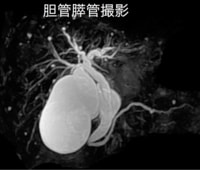

軟部組織のコントラストに優れ、様々なコントラストパラメーターを有するMRIは、頭頚部、体幹部、脊椎・脊髄、整形領域、心臓領域とほぼ全身に渡る断層画像をあらゆる角度で撮像できます。

当院導入のGE社は超伝導MRIの稼動実績において、日本だけでなく世界においてもトップシェアを維持し続けて、良質な画像を得ることが出来ます。

当院のMRIの特徴

今回当院では画像描出に定評のあるGE社の1.5TのMRIを採用しました。

この装置は光デジタル伝送技術を採用し、外部ノイズの混入を抑え、劣化のない高画質な画像を得ることができます。